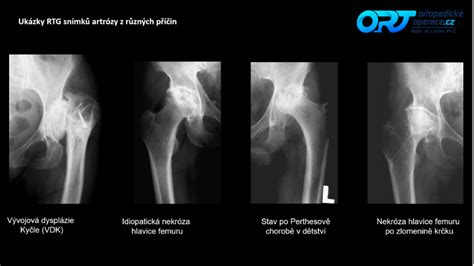

Na snímku dysplatické kyčle vás upoutá hlavně hlavice stehenní kosti, která není pevně a dostatečně hluboko usazena v kloubní jamce; nebo skutečnost, že hlavice a jamka nejsou na povrchu hladké, ale zdeformované. To může způsobit opotřebení kloubu a velké bolestivé tření při pohybu. Kyčel pak trpí nadměrnou zátěží a je náchylný na vytvoření zánětu, díky kterému se navíc může vyvinout osteoartróza, která je na RTG snímku rozpoznatelná jako malé úlomky kostí, ničící pak dále kloub.